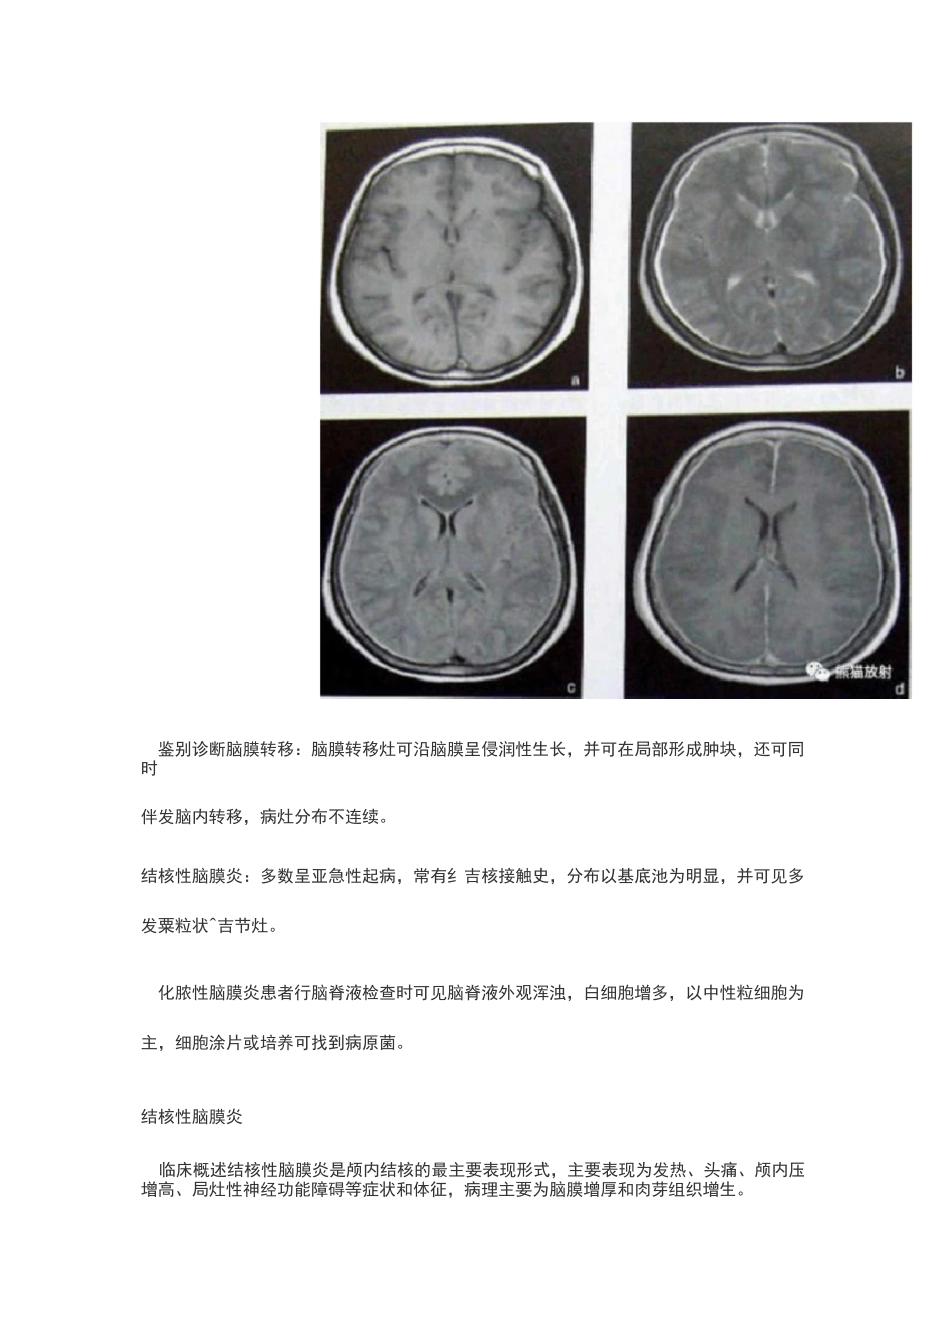

化脓性脑膜炎临床概述化脓性脑膜炎是常见的中枢神经系统化脓菌感染性疾病主要表现为发热、头痛、惊厥和颅内压增高等。表现平扫可见基底池和脑沟的正常形态消失,呈等密度改变,这是由于炎性渗出物填充脑池和脑沟所致;增强扫描可见脑膜强化;本病可并发脑积水,表现为脑室扩大;本病可并发硬膜下积液,表现为脑外新月形低密度区;本病并发脑静脉窦血栓时,增强扫描可见典型空三角征,此征象由强化的血流和血管壁与不增强的血栓共同组成;可并发出血性脑静脉梗死、脑炎或脑脓肿。鉴别诊断脑膜转移:脑膜转移灶可沿脑膜呈侵润性生长,并可在局部形成肿块,还可同时伴发脑内转移,病灶分布不连续。结核性脑膜炎:多数呈亚急性起病,常有纟吉核接触史,分布以基底池为明显,并可见多发粟粒状^吉节灶。化脓性脑膜炎患者行脑脊液检查时可见脑脊液外观浑浊,白细胞增多,以中性粒细胞为主,细胞涂片或培养可找到病原菌。结核性脑膜炎临床概述结核性脑膜炎是颅内结核的最主要表现形式,主要表现为发热、头痛、颅内压增高、局灶性神经功能障碍等症状和体征,病理主要为脑膜增厚和肉芽组织增生。,鉴别诊断表现平扫可见脑基底池和外侧裂池密度增高,增强可见脑膜强化;脑实质内多个粟粒状结节灶,呈等密度,增强扫描可见病灶强化;本病常见爆米花样营养不良性钙化,多位于基底池周围;间接征象包括脑积水、脑萎缩和脑梗死等改变脑膜转移:脑膜转移灶可沿脑膜呈侵润性生长,并可在局部形成肿块,还可同时伴有脑内转移,病灶分布不连续。化脓性脑膜炎:多急性起病,常见脑积水和硬膜下积液改变。结核性脑膜炎患者行脑脊液检查示细胞数多小于个,以淋巴细胞为主,糖含量减少,蛋白含量升高,涂片抗酸染色可找到结核分枝杆菌。病毒性脑炎临床概述本病临床表现为头痛、发热、智力减退、癫痫等症状,严重者可昏迷甚至死亡。表现病毒性脑炎早期(在发病天),表现可正常,随病情进展,多表现为颞叶境界不清的低密度病变;增强可见境界不清的斑片状或脑回状强化;病变严重者可见脑实质内不规则高密度出血灶;本病后遗症改变包括脑软化、脑萎缩和营养不良性钙化等鉴别诊断脑梗死:发生脑梗死时,其异常血管分布区与病变血管的血供区一致,增强扫描梗死区域可见轻度脑回样强化。脑肿瘤:病灶占位效应明显,增强后多呈环状或实性强化。脑脓肿临床概述急性感染症状:头痛、发热、寒战、乏力、嗜睡等;颅内压增高症状:头痛、呕吐视盘水肿;伴有不同程度的精神和意识障碍,并局限性癫痫发作;脑疝:可发生小脑幕切迹疝及枕骨大孔疝;可并发急性化脓性脑室炎或脑膜炎。表现平扫显示不规则的低密度区,边界欠清;增强扫描显示脓肿壁呈厚壁环形强化,边缘光整,中央不强化,病灶周围可见明显脑水肿。鉴别诊断慢性脑内血肿:病变可环形强化,壁可厚可薄,呈低密度或等密度,有近期急性脑出血病史。胶质母细胞瘤:可呈环形强化,壁形态不规则,可见壁结节。脑转移瘤多有原发肿瘤病史,脑内病变常多发,小病灶即可见明显的脑水肿。在脑脓肿鉴别诊断方面,应用有助于脑脓肿和脑内环形强化肿瘤鉴别,脑脓肿脓液中含大量蛋白,脓液黏稠,水分子的弥散受限,高信号,降低。肿瘤坏死及囊性肿瘤内水分增多,弥散增加,低信号,值升高。病因包括耳源性、血源性及其彳也等。直接蔓延的病灶多为单发,幕上颞叶多见,血行感染的病灶好发于皮质和皮髓质交界区,常多发;病理可分为脑炎期、化脓期和脓肿壁形成期,吧、脓肿壁内层为肉芽组织和巨噬细胞,中层为胶原纤维,外层为胶质增生。脑结核瘤临床概述脑结核瘤为结核分枝杆菌在脑部引起的慢性肉芽肿;本病起病隐袭,可表现为结核中毒症状,如低热、乏力盗汗等;本病一般以癫痫发作、精神障碍、颅内压增高为主要表现;可发生于田可年龄,成人幕上多见,可出现头痛、癫痫、偏瘫、失语等;儿童幕下多见,可出现颅内压增高和小脑共济失调等。表现成熟前期:平扫显示呈低密度区,无强化。成熟期:表现为圆形或类圆形等密度或稍高密度病灶,边界不清,周围有水肿,增强后病灶呈结节样强化。干酪样坏死期:平扫呈稍高密度或等密度区,少数可有钙化,增强后呈环形强化,表现典型者环形病灶...